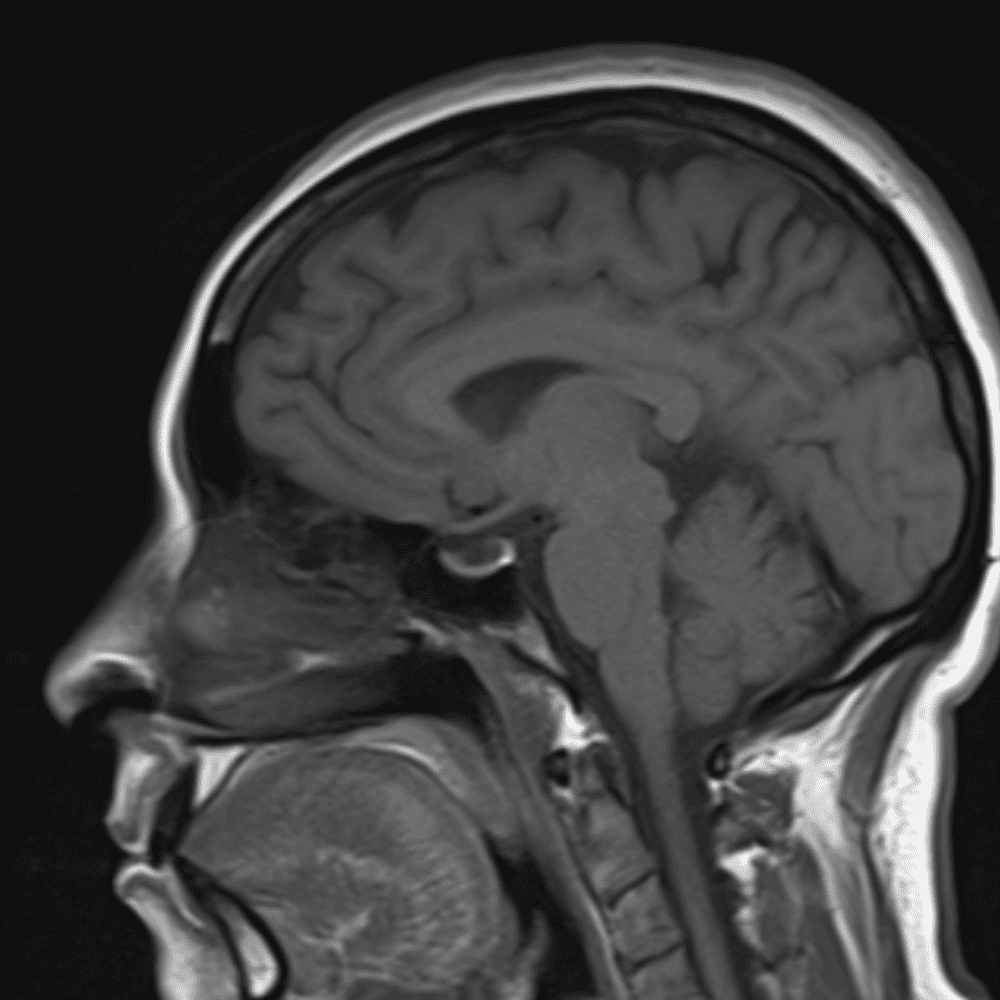

๋‹น์ง ์‹œ ํ”ํžˆ ๋ณผ ์ˆ˜ ์žˆ๋Š” ์‚ฌ๋ก€์˜ ์ „ํ˜•์ ์ธ ์˜ˆ๋ฅผ ํฌํ•จํ•ฉ๋‹ˆ๋‹ค.

39 ์‚ฌ๋ก€